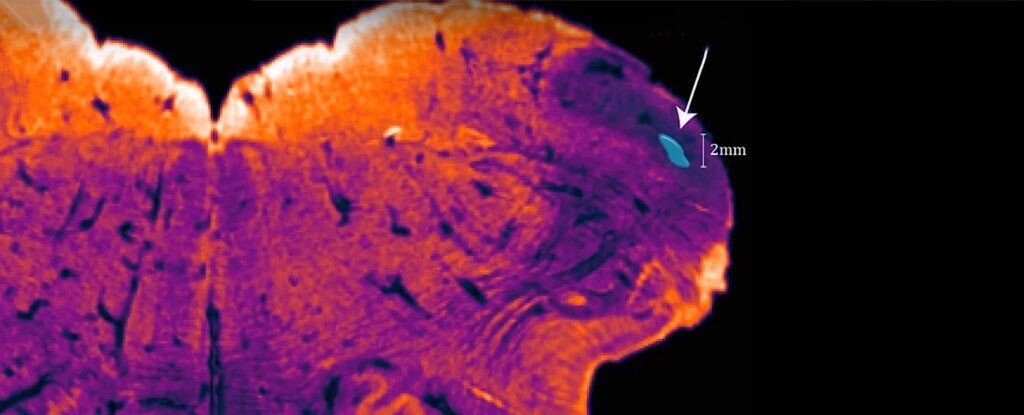

Ученые из Научно-исследовательского института Австралии (NeuRA) назвали свое открытие endorestiform nucleus, так как участок расположен внутри нижнего мозжечкового стебля. Он находится у основания мозга, где тот соединяется со спинным мозгом, и отвечает за наши осанку, равновесие и движения. «Нижний мозжечковый стебель можно сравнить с рекой, несущей информацию из спинного мозга и ствола мозга в мозжечок, в то время как endorestiform nucleus — это группа нейронов, похожая на остров в этой реке», — говорит нейробиолог Джордж Паксинос (George Paxinos), главный автор открытия. Статья еще готовится к рецензированию, однако подробности находки уже доступны в последнем атласе мозга Паксиноса. Паксинос идентифицировал эту часть мозга, используя относительно новую технику окрашивания головного мозга, которую он разработал, чтобы сделать изображения тканей мозга более отчетливыми для своего последнего атласа.  Эти окрашивающие элементы нацелены на активные продукты клетки — химические вещества

Эти окрашивающие элементы нацелены на активные продукты клетки — химические вещества в мозге — нейромедиаторы, обеспечивающие карту тканей мозга. Это помогает разделить группы нейронов по функциям, а не по их виду. Используя такую технику, еndorestiform nucleus явно выделялся на фоне остальных объектов: его «окраска» получилась более плотной, а окружающие области были представлены в негативе. Таким образом, Паксинос утверждает, что открытие само нашло его.